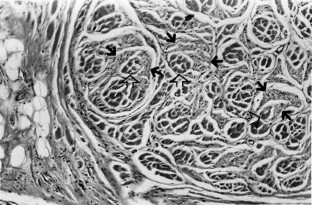

Fig. 2